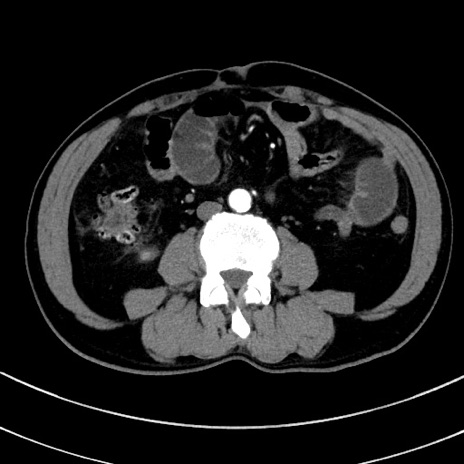

症例8(横断像)

【症例】 60歳代男性

【主訴】 黒色吐物

【現病歴】 4日前から嘔気自覚、2日前の朝食後にも嘔気あり、自分で手で嘔吐反射起こし嘔吐したところ血が混ざっていたため受診。

【既往歴】 5年前汎発性腹膜炎を伴う急性虫垂炎で手術、高血圧、前立腺肥大症、高脂血症

【身体所見】 腹部正中に手術癩痕あり 腹部平坦・軟圧痛なし膨満感あり

【データ】WBC 8400、CRP 4.54